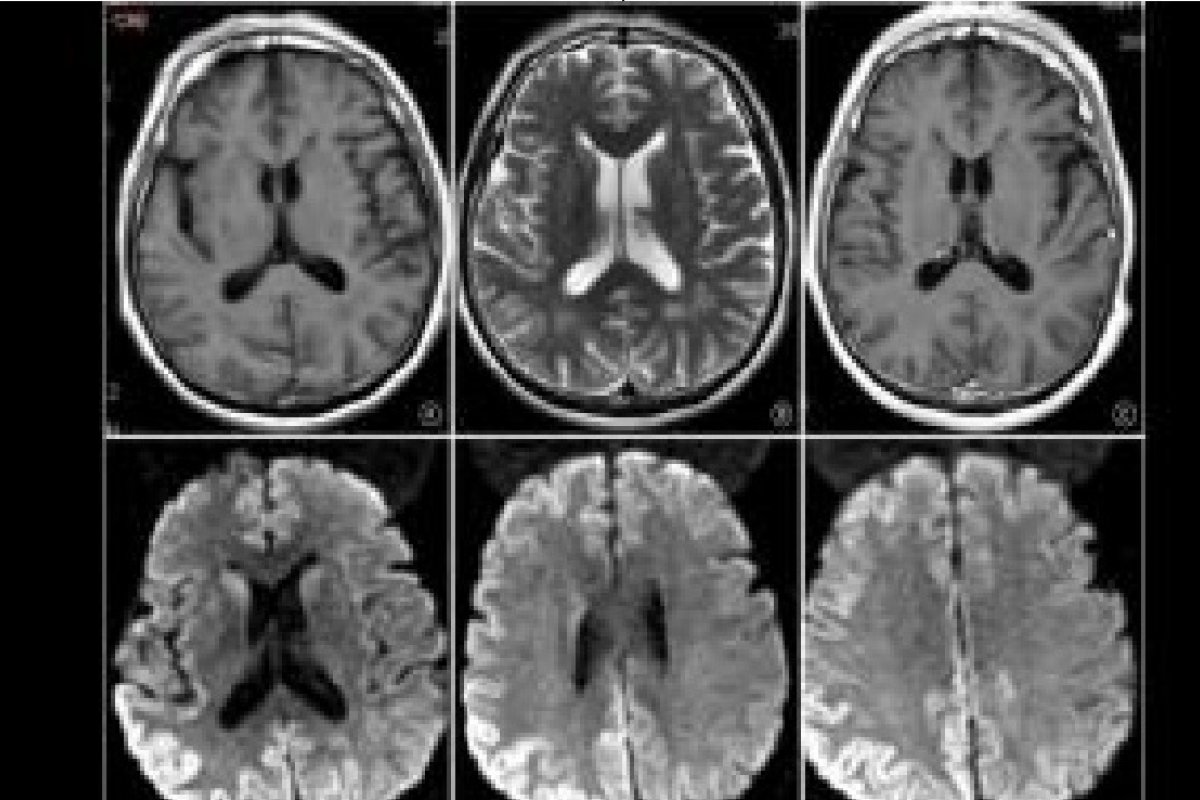

A Doença de Creutzfeld-Jakob provoca desordem cerebral, perda de memória e, de forma inevitável, leva à morte. A DCJ tem quatro tipos diferentes de manifestação.